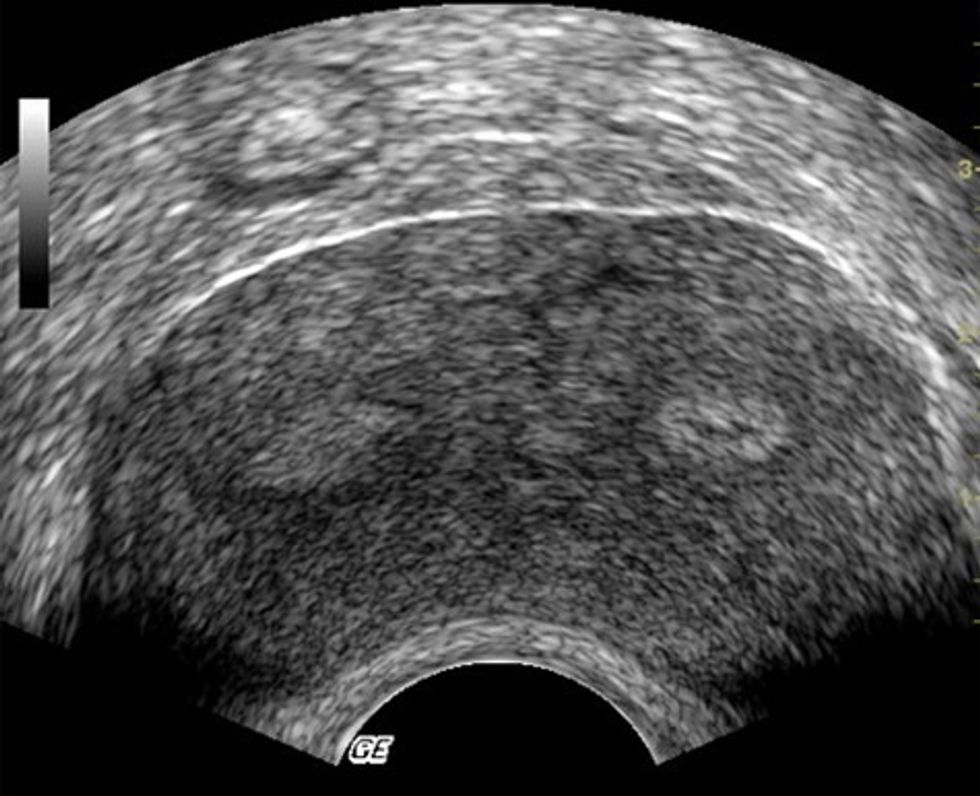

Diagnoza caktohet përmes ultrazërit ku kemi figurën e njohurs i “Sytë e hutit”: